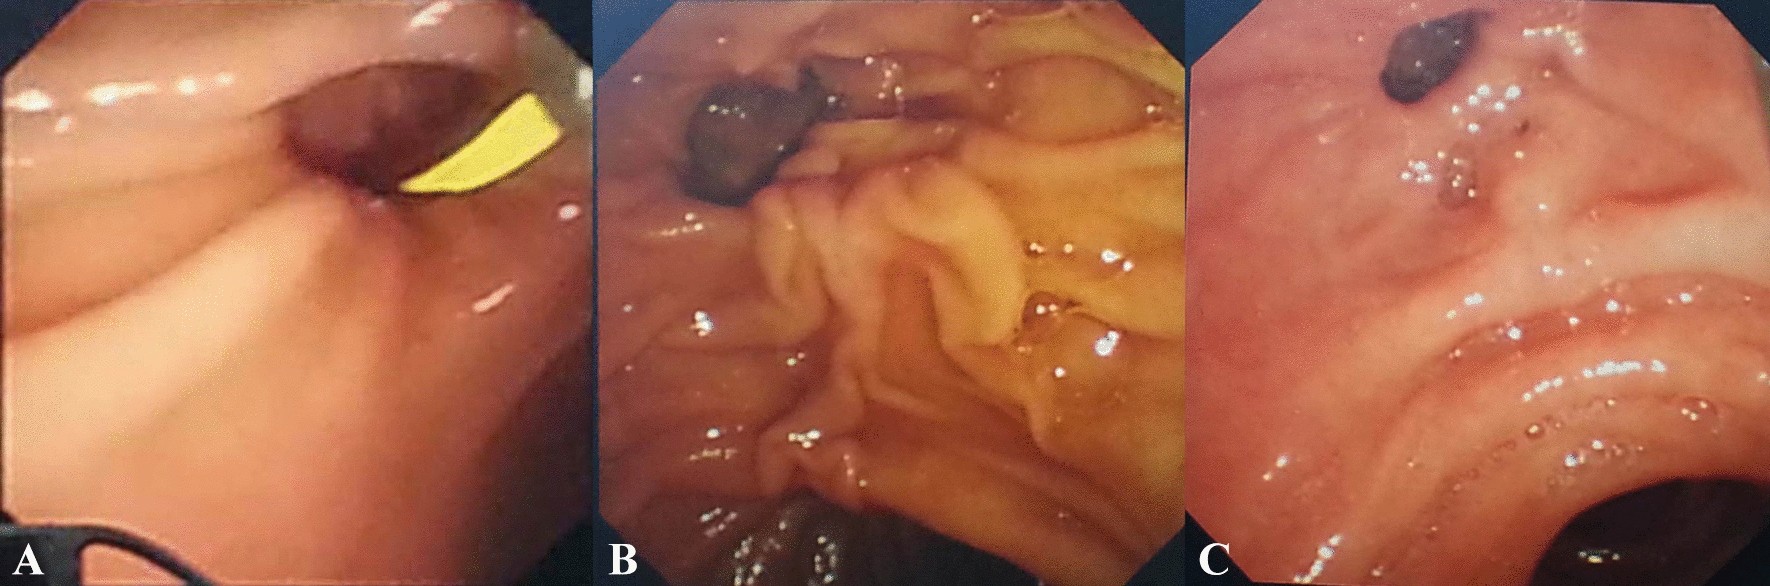

Figure 1

From: The influence of periampullary diverticula on ERCP for treatment of common bile duct stones

The locations of the major papilla with diverticula. (A) Papilla was located inside the diverticula; (B) papilla was located at the margin of the diverticula; (C) papilla was located outside the diverticula.